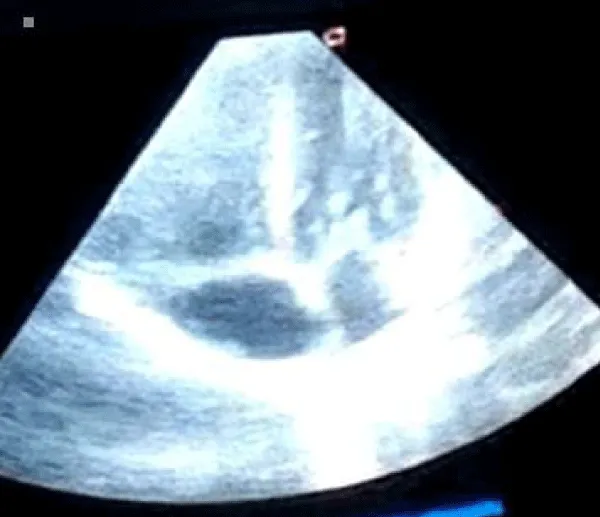

A male neonate delivered at term via SVD to a 24 years old G2P2 mother, who was diagnosed with gestational diabetes at 31 weeks of gestation who had poor glycemic control despite being on subcutaneous insulin and dietary modifications. Mother also had gestational diabetics during her first pregnancy (deranged glycated haemoglobin HbA1c) and claimed her blood sugar normalized after delivery. Her first child was a female and weighed 4.5 kg, alive and well and did not have any immediate neonatal complications. No family history of cardiac diseases. Birth weight of index baby was 4.8 kg (> 95% centile for age) and Apgar scores were 5/7/7 in 1, 5 and 10 minutes respectively. The physical examination showed a macrosomic infant (weight > 95% centile for age), thick upper extremity skin folds, broad shoulder and torso with a relatively smaller head, and plethoric look. He had respiratory distress with peripheral cyanosis. Oxygen saturation (SPO2) was 92% (room air) and urgent random blood sugar (RBS) was 4.6mmol/l. There were no other obvious malformations. Baby was admitted immediately after birth into the special care baby unit (SCBU) of a Federal Medical Centre in southern part of Nigeria for moderate birth asphyxia, severe respiratory distress and macrosomia. Child had persistent respiratory distress while on admission and further cardiac evaluation revealed displaced apex beat with no cardiac murmur. Chest x-ray done showed severe cardiomegaly with bi-ventricular and right atrial enlargements and a cardiothoracic ratio of 68% and oligaemia (Figure 1). Electrocardiography showed evidence of biventricular hypertrophy, right atrial enlargement, sinus tachycardia and occasional premature ventricular complexes (Figure 2). Echocardiography done on the 7th day of life showed severe bi-ventricular hypertrophy with significant narrowing of the left ventricular cavity, marked asymmetrical septal hypertrophy, moderate to severe dynamic subaortic stenosis (Peak gradient 45 mmHg) and left ventricular systolic and diastolic dysfunction (Figure 3). He was commenced on tabs propranolol at 1mg/kg/dose 8hrly and discharged after 5 days with improvement in respiratory distress. He also received oxygen therapy, intravenous fluid and intravenous antibiotics as well as intensive nursing care while on admission. Follow up echocardiography at 6 wks of life showed evidence of remarkable resolution of hypertrophy and improvement in ventricular function (Figure 4).

Download Image

Figure 4: Repeat Echocardiography at 6 weeks of life (apical 4 chamber view) showing significant improvement in ventricular wall and septal enlargement.